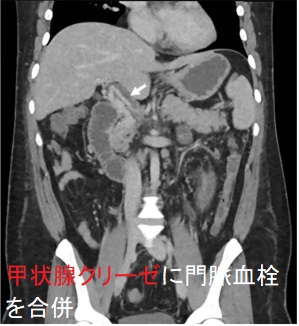

甲状腺クリーゼに肺血栓塞栓症(肺梗塞)だけでなく、腸骨静脈・大腿静脈血栓、門脈血栓を合併した報告もあります[Endocrinol Diabetes Metab Case Rep. 2021 Jan 11;2021:20-0118.]

- 胸部造影CTでほぼ確定